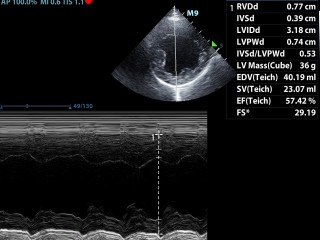

Echografie hart

Toen onze oude echoapparaat vervangen moest worden hebben we ervoor gekozen dat bij ons nieuwe echo apparaat het ook mogelijk moest zijn om echo onderzoeken van het hart te maken. Er moet dan o.a. doppler opzitten en je moet een ECG kunnen aansluiten, ook zijn de eisen voor de kwaliteit veel hoger. Onze nieuwe Mindray M9 voldoet aan deze eisen en heeft een zeer gevoelige en nauwkeurige echo detectie.

Dierenarts Rianne Compagner maakt de hartecho's, zij heeft diverse cursussen en nascholingen hiervoor gevolgd.

Het hart in beeld

Hieronder zie je een aantal foto's van het hart.